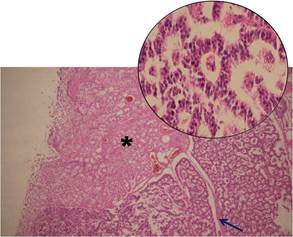

Además, en el estudio macroscópico del intestino, se observó a nivel de la primera porción del duodeno lesión de consistencia firme, ligeramente elevada de la superficie de aspecto polipoidea de 1 cm de diámetro, con una superficie de corte de color amarillo claro; al realizar el estudio histológico, se observó una lesión a nivel de la submucosa con revestimiento de la mucosa indemne (Figura 1).

Dicha lesión estaba compuesta por islotes separados por un estroma fibrovascular, las células adoptaban una disposición en forma de rosetas, aunque hacia la periférica se observaron áreas más sólidas; las células eran uniformes con núcleos pequeños y redondeados, con una cantidad moderada de citoplasma eosinófilo; no se observan mitosis ni necrosis (Figura 2).